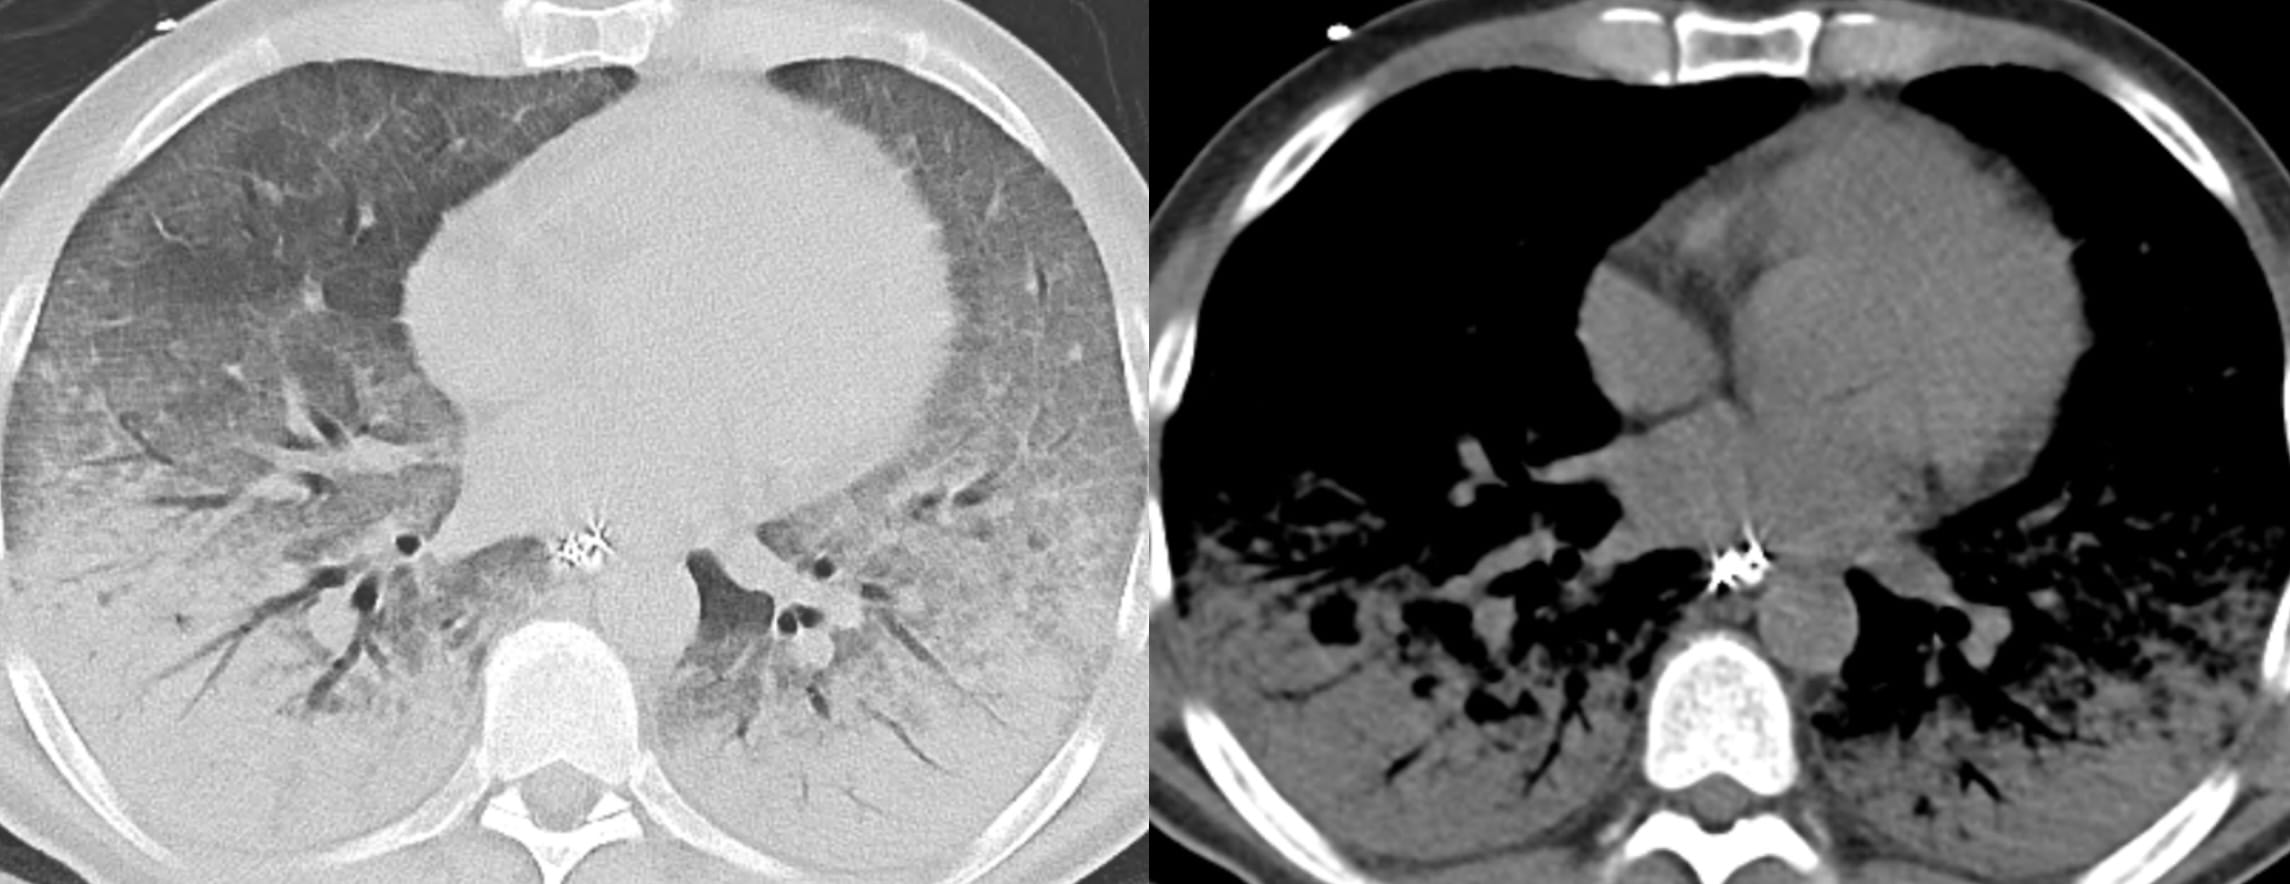

CT of Acute Lung Injury Edema

Don’t confuse the posterior lung opacities with anything else other than consolidated and —particularly—atelectatic lung. This is potentially so-called recruitable (by different ventilatory strategies) lung.

The concepts of (dorsal) “sponge” and (ventral) “baby” lungs are evocative. The size of the ventral aerated lung in ARDS (with the patient supine) suggests a “baby” lung— as conceptualized by Gattinoni et. al.

There is relatively more lung volume in the dorsal lungs.